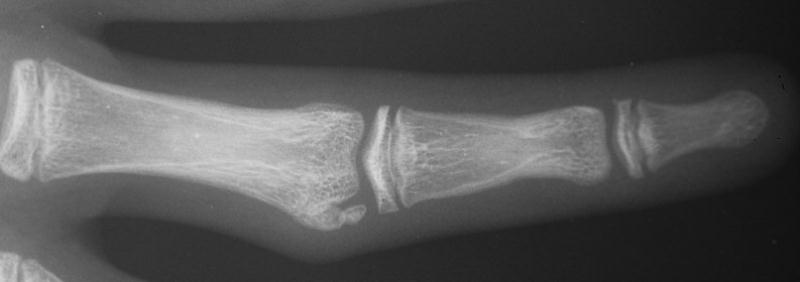

Case 2. Mass developing after a lateral dislocation of the proximal  interphalangeal joint of a 34 year old woman.

Radiographs were consistent with either a united collateral ligament avulsion fracture or ossiification of a parosteal hematoma.

This was treated with simple excision and collateral ligament repair to local tissues.